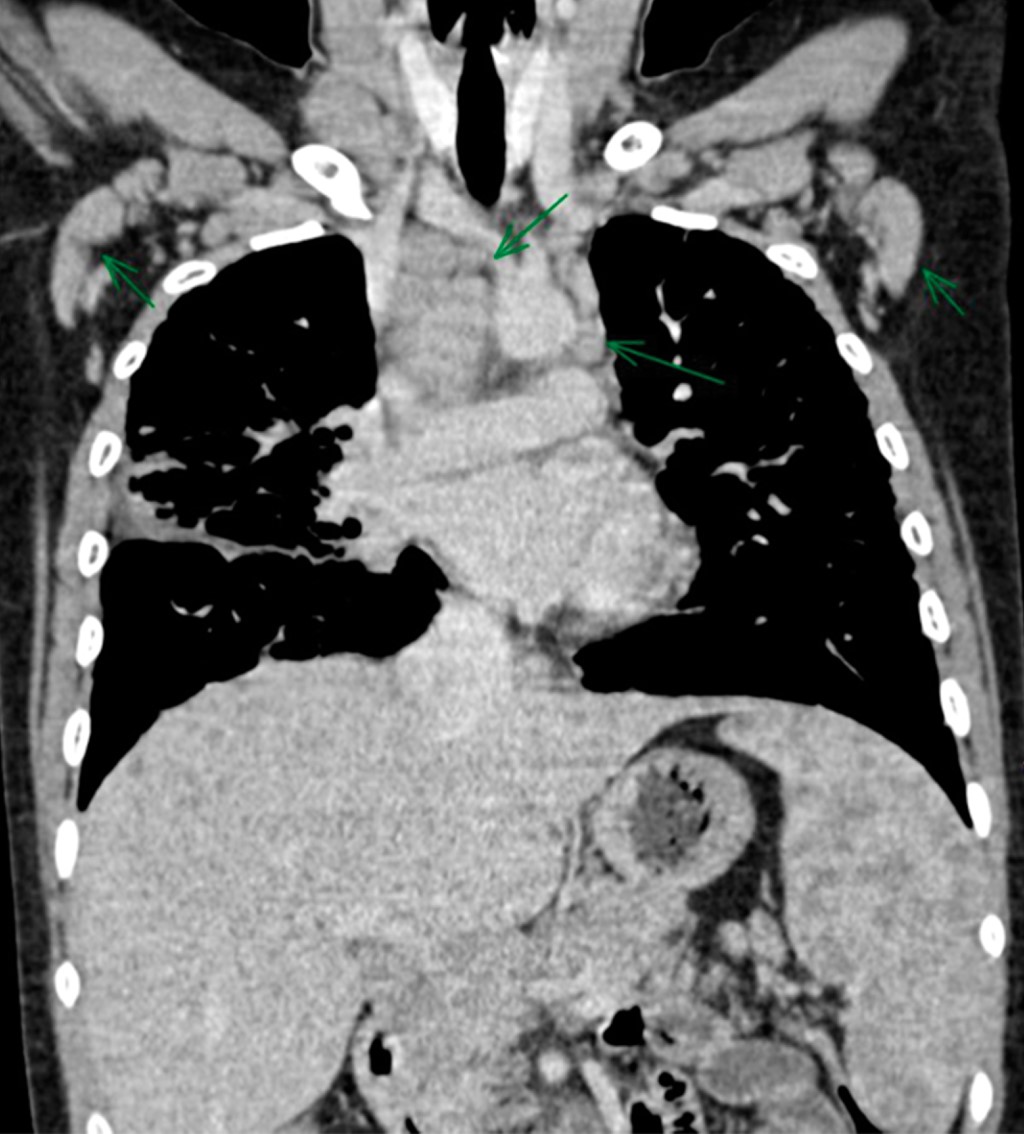

La radiografía de tórax mostró ensanchamiento mediastinal y un patrón intersticial grueso a expensas de intersticio perilobulillar bilateral y difuso, casi simétrico con algunas imágenes nodulares también difusas (Figura 9). En la TACAR contrastada se corrobora el patrón intersticial perilobulillar con nódulos difusos con discreto predominio subpleural así como zonas de atelectasia bilateral subpleurales y en lóbulo medio (Figura 10). En la ventana mediastinal se demuestran crecimientos ganglionares paratraqueales de predominio derecho, en ventana aortopulmonar y axilar bilateral. A nivel abdominal lesiones nodulares hipodensas múltiples hepatoesplénicas sugestivas de granulomas (Figura 11). Se realizó biopsia de piel en cara, la cual mostró dermatitis granulomatosa epitelioide no caseificante, compatible con sarcoidosis (Figura 12).

La radiografía de tórax es anormal en 90% de los casos. Los dos hallazgos más característicos son la linfadenopatía mediastinal bilateral acompañada de enfermedad intersticial nodular del pulmón, éstos sirven para la estadificación de la enfermedad,5,8 siendo la TACAR la herramienta más valiosa para el diagnóstico (Tabla 1).

Nuestros casos se clasifican en el estadio II, ya que en la TACAR se detectó adenopatía hiliar bilateral con infiltrados pulmonares (Tabla 1).

Figura 9

Figura 10

Figura 11

Figura 12